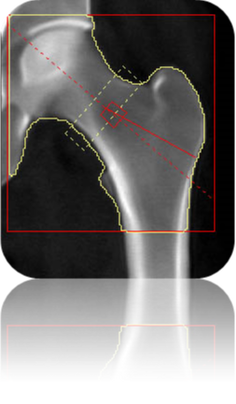

- Última generación de Densitometría con energía dual.

- Evalúa el riesgo de fracturas y futuras enfermedades óseas.

- Sistema de rayos X de pulso accionado de doble energía (100 kVp / 140 kVp)

- Técnicas de adquisición rectilíneas que ofrece excelente calidad de imagen y precisión.